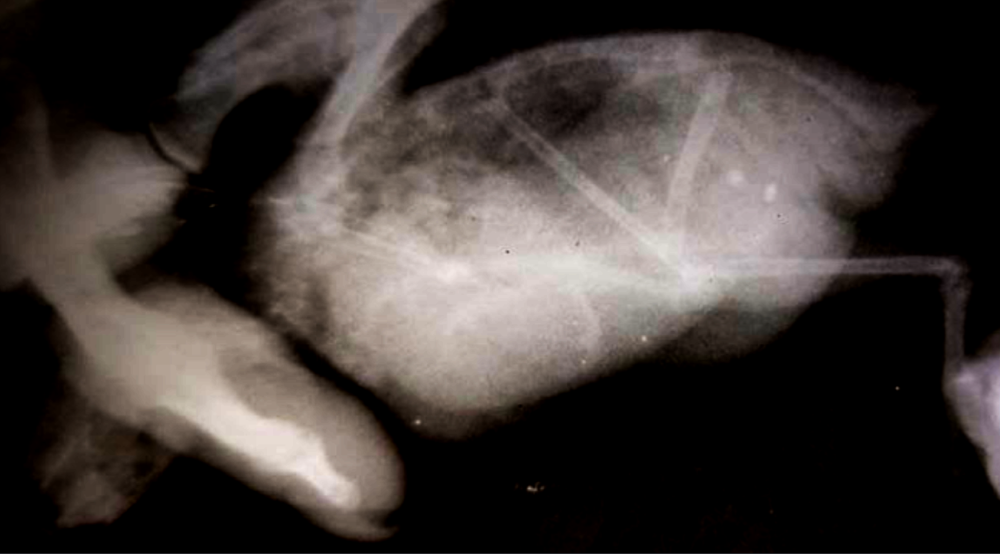

по анализу- слабо выраженная недостаточность поджелудочной.

По рентгену- максимум что смогла выжать из снимка покажу ниже.

Семенников не видно как органа.

Практически вся целомическая полость занята образованием, не имеющим очерченной поверхности (возможно не одним).

Велика вероятность н/о семенников, возможно вторичным , а первичное- печень.

степан 2.png